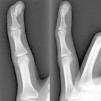

The patient is a 29-year-old woman, who complains of swelling and pain in the fifth finger of the left hand lasting for 3 months. She had no medical history and no previous trauma of the referred finger. On examination, she presented a tumor of 1.5cm×0.5cm on the tip of the finger and the subungual region, of indurated consistency which adhered to deep planes, with mild erythema and tenderness. Radiological studies showed a well-circumscribed, nodular ossified lesion with irregular borders, adhered to the l periosteum of the distal phalanx, without erosion of the cortex (Fig. 1). Laboratory studies, including biochemistry, hematology and acute phase reactants were all normal. Excision of the lesion was performed and the histopathological study revealed fibrous tissue and fibroblasts with prominent nuclei without atypia in its periphery, and immature osteoid deposits surrounded by an osteoblastic rim in the central area (Fig. 2). These findings were consistent with the diagnosis of florid reactive periostitis of the hand (FRPH). There was no recurrence of the lesion.

FRPH is a rare benign entity characterized by a lush production of osteoblastic proliferative fibrous stroma in the periosteum of the fingers.1 Its pathogenesis is unknown but is considered to correspond more to a reactive process than to a neoplasm, with a history of trauma being present in up to 50% of cases.2 Although it was described in 19333 there still is confusion in the literature caused by different denominations, including paraostal fasciitis, ossifying fasciitis, fibro-osseous pseudotumor, pseudomalignant bone tumor of the soft tissue of the fingers and nodular fasciitis, with FRPH being the accepted term.2,4 It is most frequently located in the proximal phalanx, followed by the middle phalanx, metacarpal joints and distal phalanx; it is rare in the first two fingers. It usually occurs in women during the second and third decades of life, and is clinically characterized by swelling, pain and erythema of the affected finger.2,5 Radiographs show increased soft tissue and periosteal new bone formation, which may have a lamellar or mature bone5 appearance. The cortex is usually intact, although erosions have been occasionally described.6 The differential diagnosis includes infections (septic tenosynovitis, soft tissue abscess with bone involvement, cortical osteomyelitis), myositis ossificans, benign tumors such as giant cell tendon sheath tumors and osteochondroma, and malignant ones such as the paraostal and periosteal osteosarcoma, synovial sarcoma and periosteal chondrosarcoma.1,5 The recommended treatment is local excision, which is curative in most cases.5 In conclusion, although FRPH is an uncommon lesion, it should be taken into account because it can simulate other more serious conditions such as malignant bone neoplasms.